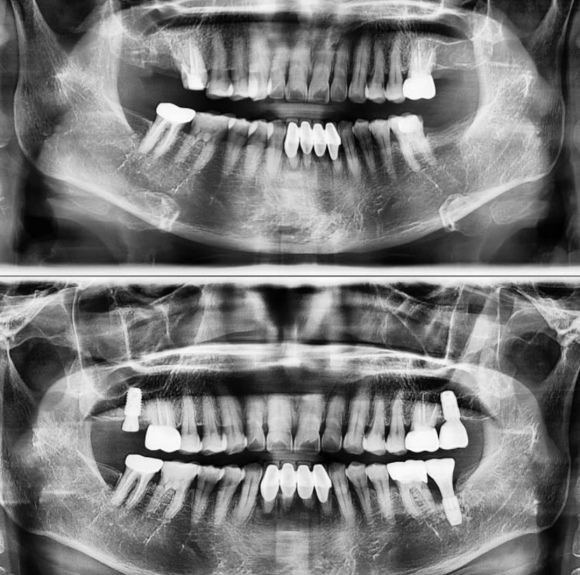

상기 환자 1년 동안 임플란트 3개와 크라운 1개를 진행 한 환자 입니다. 어금니 회복을 적절하게 진행하고 있습니다. 60대로 음식물 저작이 가장 중요하시기 때문에 반드시 잘 회복시켜 드려서 영양 섬취에 문제 없도록 할 것입니다. #상도동에서임플란트가장많이하는치과, #숭실대치과, #상도동치과, #동작구치...

상기 환자 1년 동안 임플란트 3개와 크라운 1개를 진행 한 환자 입니다.

어금니 회복을 적절하게 진행하고 있습니다.

60대로 음식물 저작이 가장 중요하시기 때문에

반드시 잘 회복시켜 드려서 영양 섬취에 문제 없도록 할 것입니다.